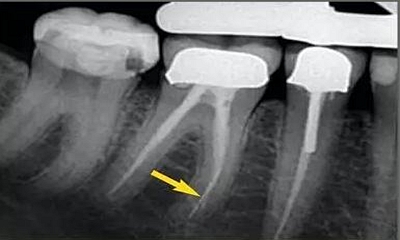

從近遠(yuǎn)中向的X光片可以看出,在根尖三分之一區(qū)域,根管形態(tài)較寬而且彎曲。通過(guò)彎曲之后,單只銼沿直線到達(dá)根尖,沒(méi)有清理的根管的唇側(cè)部分。遺漏的區(qū)域在近遠(yuǎn)中向的X光片中顯示得格外清晰。